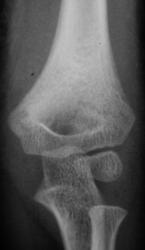

Пол пациента: Мужской пол Тип патологии: Травма Область исследования: Скелетно-мышечная система Методы исследования: Rg Рентгенограммы произведены в "ургентном" порядке ургентным лаборантом. Пациент направлен на исследование дежулным хирургом. ВАШЕ МНЕНИЕ КОЛЛЕГИ? TRAVMA.1..JPG TRAVMA_2..jpg TRAVMA.3..jpg TRAVMA.4..JPG TRAVMA.5..JPG AttachmentSize TRAVMA.1..JPG45.46 KB TRAVMA_2..jpg78.72 KB TRAVMA.3..jpg82 KB TRAVMA.4..JPG57.79 KB TRAVMA.5..JPG76.83 KB Mon, 16/11/2009 - 18:06 #1 v1tal Offline Last seen: 4 years 10 months ago Joined: 07.06.2008 - 19:41 Posts: 1779 Супракондилярный перелом дистального эпифиза плечевой кости, с незначительным угловым смещением открытым кзади. "Знаешь, у некоторых врачей есть комплекс мессии — им необходимо спасать мир. А у тебя комплекс Рубика — тебе необходимо решать головоломки." Mon, 16/11/2009 - 22:39 #2 В.Б. Серов Offline Last seen: 3 weeks 6 days ago Joined: 16.07.2008 - 10:15 Posts: 1361 Перелом вижу, смещения - нет Зри в корень! Mon, 16/11/2009 - 23:06 #3 Анатолий Владим... Offline Last seen: 7 years 10 months ago Joined: 16.10.2009 - 21:16 Posts: 1941 А смещение действительно минимальное.

Супракондилярный перелом дистального эпифиза плечевой кости, с незначительным угловым смещением открытым кзади.

Перелом вижу, смещения - нет

А смещение действительно минимальное.